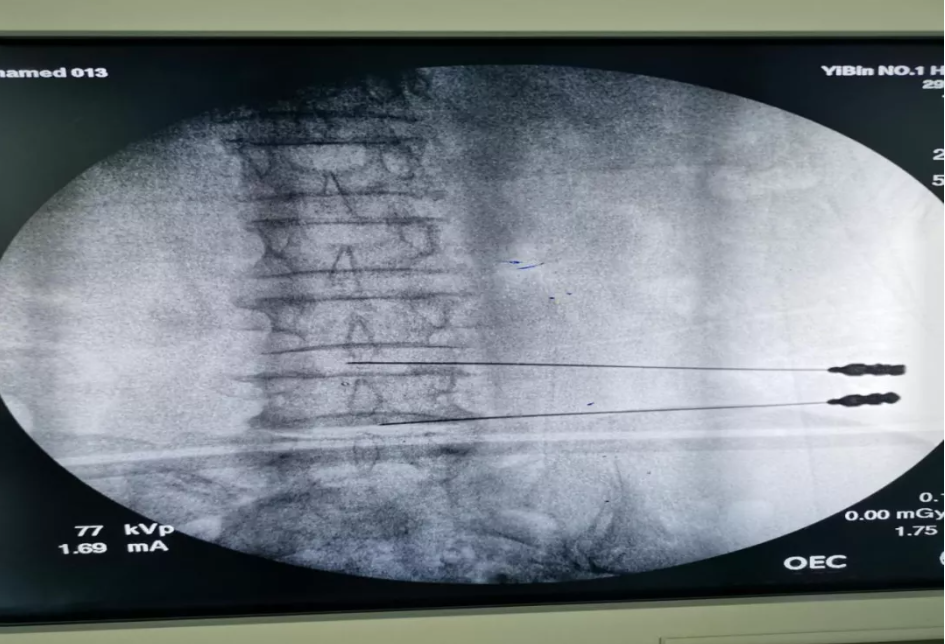

经过详细的体格检查及核磁共振辅查,患者确诊为腰椎间盘突出症。

宜宾市疼痛病学诊疗中心首席专家,宜宾市一医院特聘专家刘延青教授经综合评估,提出了腰椎间盘臭氧消融及胶原酶化学溶解术的治疗方案。

经过周密的准备,手术如期进行,术中刘教授凭着丰富的经验、精准的操作很快就完成了手术。术后第二天,患者疼痛明显缓解,现已康复出院。

刘刘延青介绍,该手术通过仪器确定病变椎间盘,然后再把针穿刺到病变位置,注射药物达到消除病因的目的。由于药物消除了炎症、水肿,减除了椎间盘对神经的刺激,病人的症状就可以得到非常好的缓解。”